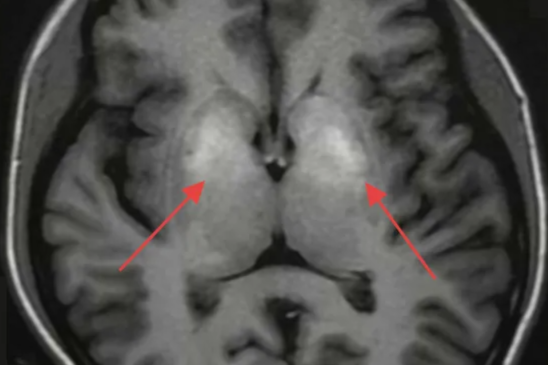

南科大医院成功救治肠瘘合并韦尼克脑病危重患者